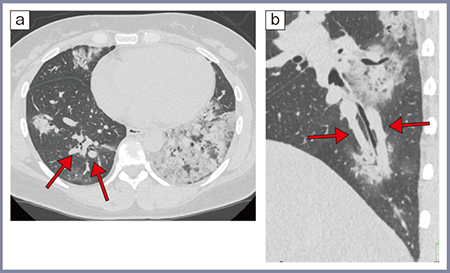

肺がんの報告からもわかるように,高精細CTでは,終末細気管支から呼吸細気管支にかけての小葉中心構造が,従来CTよりはっきり認識できる。この結果,従来CTでは小葉間隔壁で囲まれたMillerの二次小葉までしか認識できなかったが,高精細CTでは,気管支の分岐パターンで定義されているReidの二次小葉が認識可能となった(図1)2)。正常な肺では,Reidの二次小葉は肺のどの領域でもほぼ1cm程度の大きさであることがわかっており,これを利用すれば局所の肺の容積減少が評価できる。

例えば,図2に示すようにCOVID-19肺炎では病変部分(b)の二次小葉が正常部分(c)に比較して小さいが,これは局所の肺胞の虚脱を反映する所見と考えられる3)。

図2 60歳代,女性,COVID-19肺炎(2020年の症例)3)

a:高精細CT軸位断像 b:病変部分の冠状断拡大像 c:正常部分の拡大像